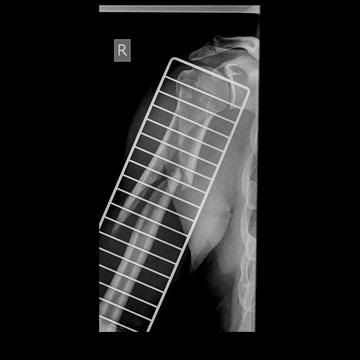

Broke my arm

9 days ago. Fall at work offshore in Nigeria. 12 weeks off work now